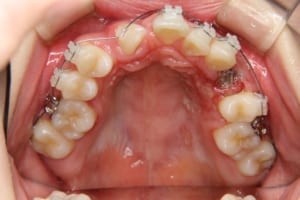

治療中

その他/備考 上顎右側中切歯および側切歯が、埋伏していた犬歯によって歯根吸収していました。

牽引に半年かかりました。